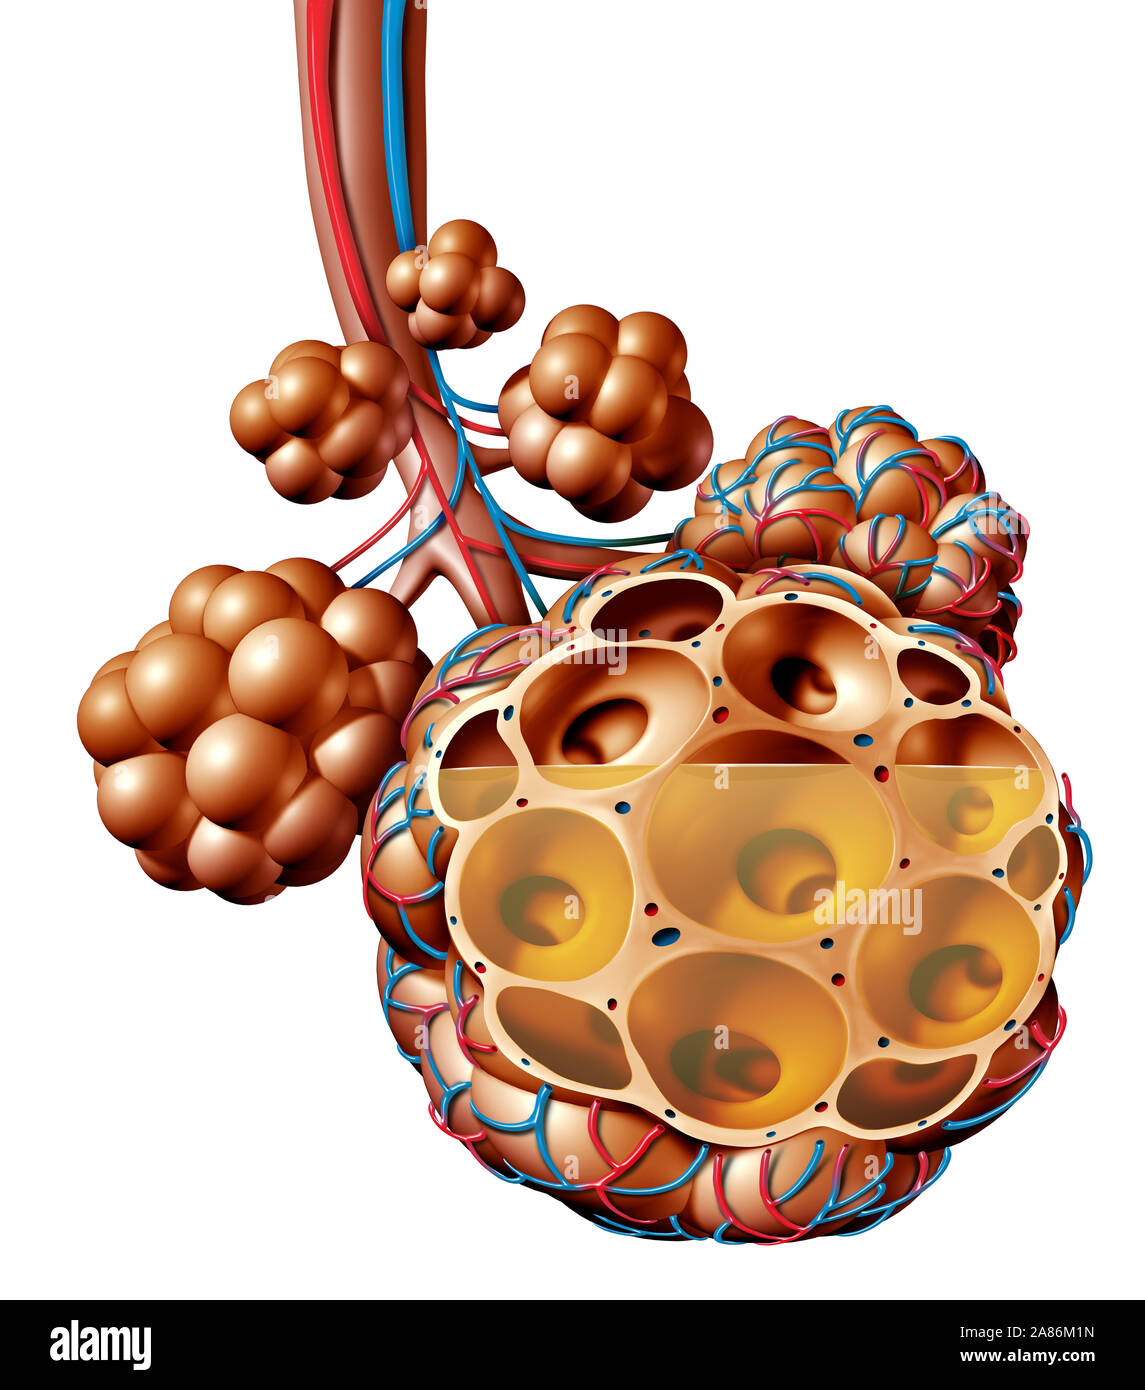

RF2A86M1N–La pneumonie et alvéoles pulmonaires de liquide ou de l'anatomie de l'inflammation alvéolaire du schéma d'un concept médical anatomie pulmonaire et respiratoire.

RF2A895XN–La pneumonie et alvéoles pulmonaires avec schéma fluide ou inflammation alvéolaire schéma anatomique comme un concept médical des poumons sains et malsains.